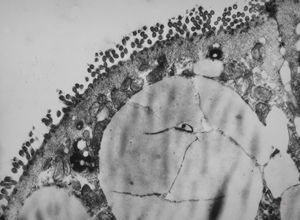

M,54y. | Whipple disease

Whipple disease